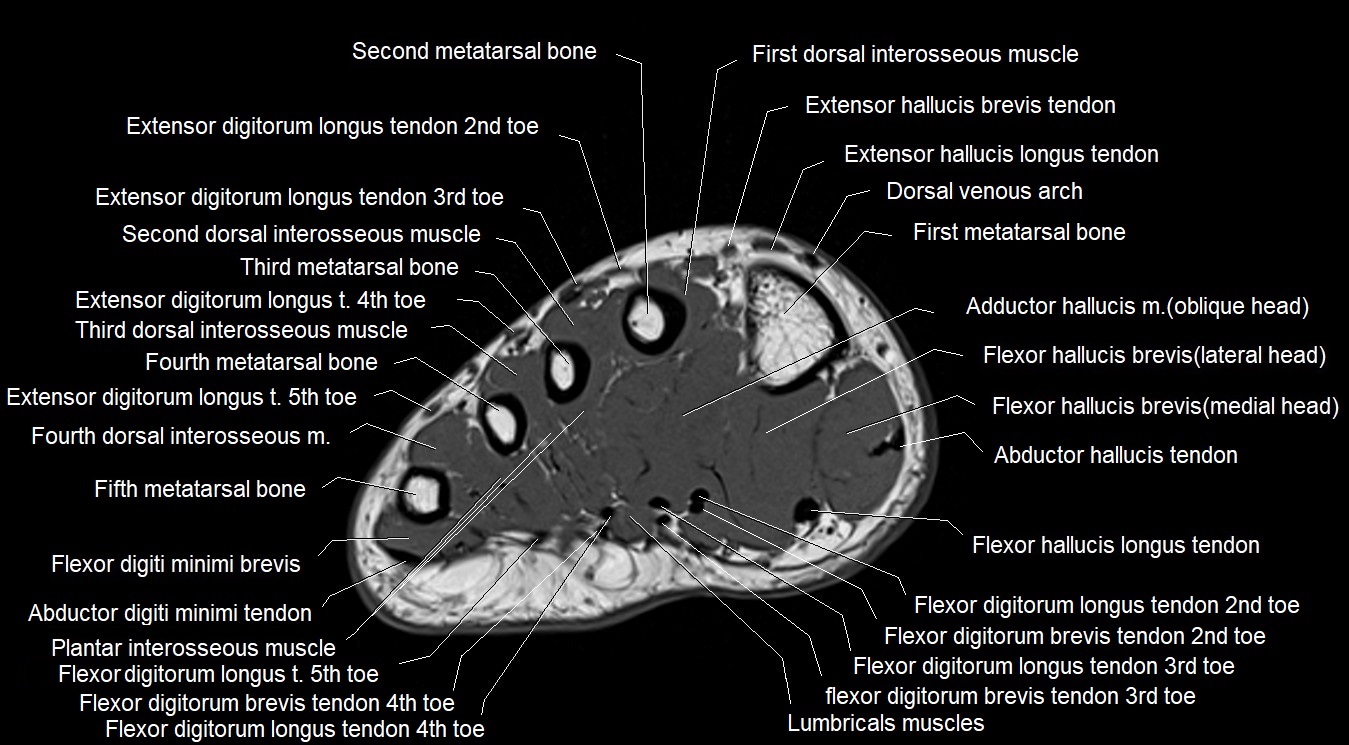

MRI image